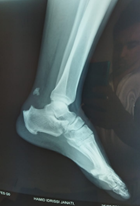

A 50-year-old male, who was diabetic and on insulin, sought medical attention for an acute distal rupture of the left calcaneal tendon. The patient was under observation for 12 months due to tendinopathy. Initially, the tendinopathy was treated with analgesics and anti-inflammatory medications; however, there was no improvement. Following this, a corticosteroid infiltration was done. The patient reported experiencing the typical symptoms of a calcaneal tendon rupture during an abrupt acceleration. These symptoms included a cracking sound that resembled a kick in the lower calf, discomfort in the hindfoot, and functional impotence of the lower limb. A positive Thompson sign, a loss of physiological equinus, and a distal notch were identified during the clinical examination of the tendon path. A bone avulsion of the calcaneal tuberosity was observed on the lateral ankle radiograph (Figure 1).

Figure 1 The lateral ankle radiograph showed a bone avulsion of the calcaneal tuberosity.